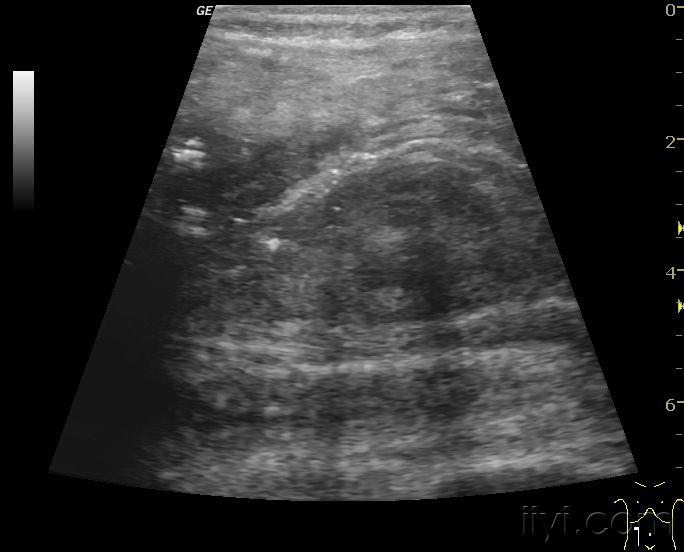

发几张自己做的小儿肠套叠的图,比较典型 - 超声医学讨论版 - 爱爱医

图片尺寸768x576